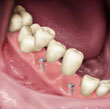

Carga Imediata

Para muitos pacientes, a necessidade de estar sem a prótese durante um período de tempo, após a instalação dos implantes, pode ser considerada inconveniência em função do convívio social e atividades profissionais. O termo carga imediata pode ser definido como instalação de implantes osseointegrados em condições ideais à estabilidade primária, seguida de ativação protética ( colocação dos dentes ) 48 horas após a cirurgia. Esta definição era aplicada à instalação de múltiplos implantes dentários e a contenção entre os mesmos promovendo um efeito de estabilidade. Com estudos recentes podemos colocar o implante unitário e colocar o dente no mesmo instante, sendo observado somente uma boa estrutura óssea.

O tratamento para colocação de implante é seguro?

O planejamento e a boa indicação de cada técnica que se utiliza é o grande diferencial do sucesso previsível. A técnica de carga imediata sem dúvida é uma ótima indicação para situações em que a quantidade e qualidade ósseas e os hábitos oclusais sejam favoráveis a sua aplicação.

Quanto tempo leva para ser feito ?

O processo leva cerca de 2 ou 3 dias variando de acordo com o número de dentes a serem implantados no paciente. Em reabilitações totais, na média, são realizados 6 a 8 implantes para cada arcada ( superior ou inferior ) em uma única sessão cirúrgica. Com o modelo em mãos é confeccionada a infra-estrutura que é provada em uma sessão, normalmente no dia seguinte a cirurgia. A infra-estrutura volta ao laboratório onde recebe os dentes. Depois a peça pronta é colocada.

A utilização de implantes unitários com procedimentos de carga imediata é discutível, porém em situações isoladas, nos quais fatores clínicos e gerais do paciente favorecem tal indicação, há possibilidade da instalação de elementos unitários, com o acompanhamento periódico regular , durante e após o processo de osseointegração, realizado também nos demais casos.

Podemos prever o resultado ?

Observando o estudo comparativo entre a técnica convencional estabelecida por BRANEMARK e o protocolo de carga imediata temos como grandes vantagens a diminuição do tempo das consultas e a rapidez dos resultados oferecidos ao paciente, com efeito psicológico e social melhorados, já que os resultados geram bem estar funcional e estético. Os pacientes devem ser selecionados e a indicação estabelecida após controle sistêmico da saúde e das condições locais favorecidas para essa técnica. Comparada com a técnica convencional onde o paciente esperaria normalmente de 3 a 6 meses para a colocação dos dentes, a técnica da carga imediata pode ser uma ótima opção.